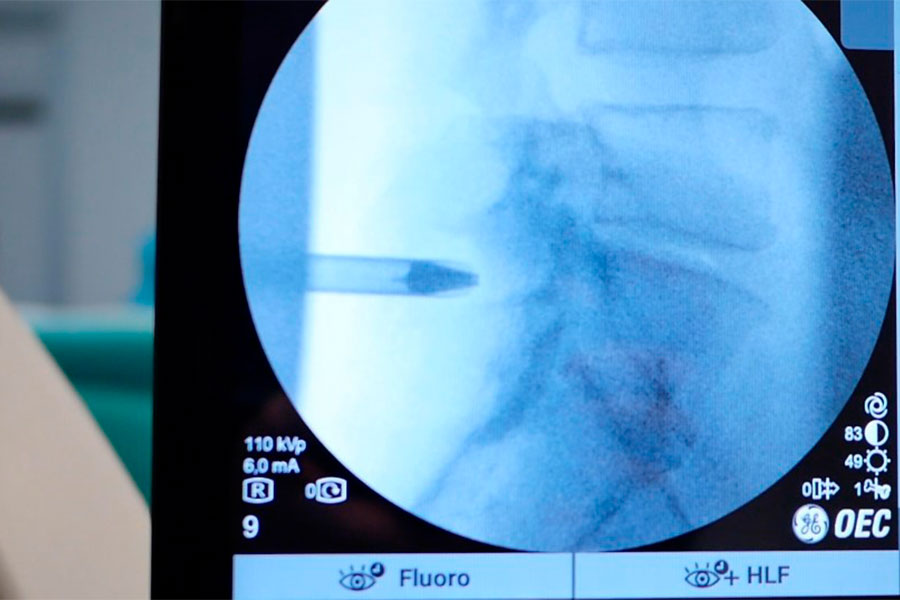

Mediante una cirugía mínimamente invasiva, se procede a la descompresión y se retira la hernia. Se lleva a cabo el sellado del disco y se suministra antiinflamatorio en la zona. La cirugía tiene una duración de quince minutos.